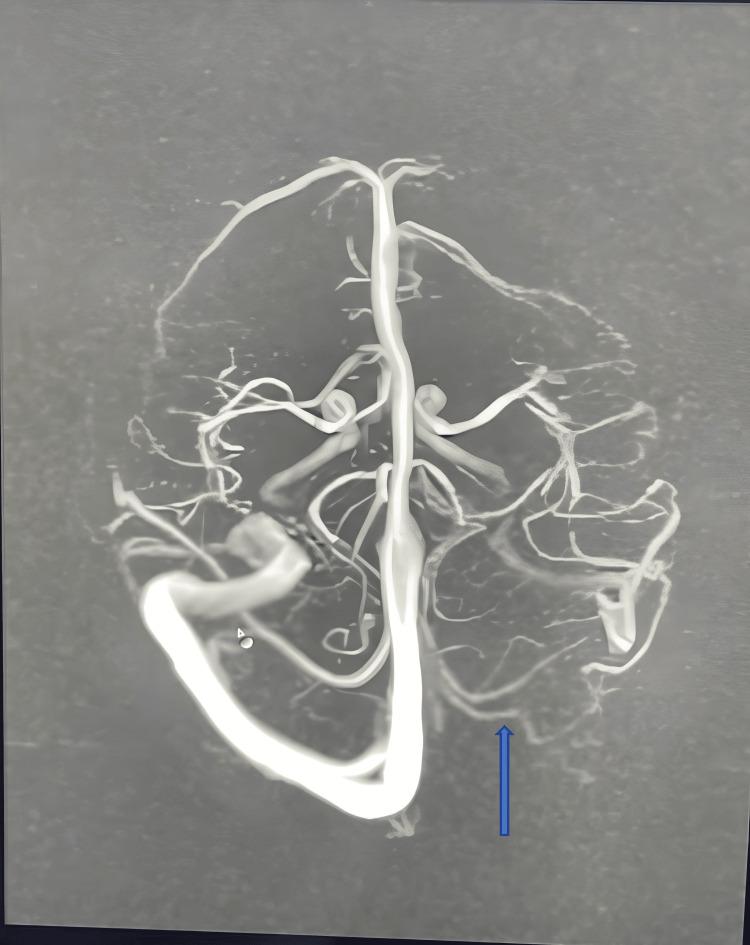

According to the literature, transverse sinus hypoplasia is not a normal variant and has a serious potential effect on cerebral blood flow. We are presenting a rare case of chronic headache due to severe hypoplasia of the left transverse and sigmoidal sinus. A 12-year-old female girl was admitted with a complaint of gradual progressive severe headache, throbbing in nature, confined to a bitemporal and frontal region in the last 4-5 months. Headache is not associated with fever, vomiting, photophobia, or vision problems. The child had no history of recurrent running nose, refractory vision, ear discharge, head trauma, exanthemata rash, or any drug history. On examination, the child was conscious and oriented. Vital signs are normal. The child was neurologically normal and had no focal signs. Other systemic examinations were normal. Based on History and examination, differential diagnosis was made, like Pseudo tumor cerebri, migraine, deep vein sinus thrombosis, and functional and Posterior fossa tumor. The child had normal routine investigations like complete blood count, electrolyte, and D-dimer. The fundoscopy was normal. In MRI, brain hypoplasia of the left transverse and sinusoidal sinus was suspected and confirmed by MRI venography. Thus, for any patient in an emergency with a chronic headache without focal signs and normal fundoscopy, one deferential should be considered for transverse and sigmoid sinus hypoplasia.

根据文献记载,横窦发育不全并非正常变异,对脑血流有严重的潜在影响。我们报告一例罕见的因左侧横窦和乙状窦严重发育不全导致慢性头痛的病例。一名12岁女童因逐渐加重的严重头痛入院,头痛呈搏动性,在过去4至5个月局限于双侧颞部和额部区域。头痛与发热、呕吐、畏光或视力问题无关。该患儿无反复流涕、难治性视力问题、耳漏、头部外伤、皮疹或任何用药史。体格检查时,患儿意识清醒、定向力正常。生命体征正常。神经系统检查正常,无局灶性体征。其他系统检查也正常。根据病史和检查结果,进行了鉴别诊断,如假性脑瘤、偏头痛、深静脉窦血栓形成、功能性疾病和后颅窝肿瘤。患儿血常规、电解质和D - 二聚体等常规检查正常。眼底检查正常。在MRI检查中,怀疑左侧横窦和乙状窦发育不全,并通过磁共振静脉造影得以证实。因此,对于任何急诊中出现慢性头痛且无局灶性体征、眼底检查正常的患者,应考虑横窦和乙状窦发育不全这一鉴别诊断。